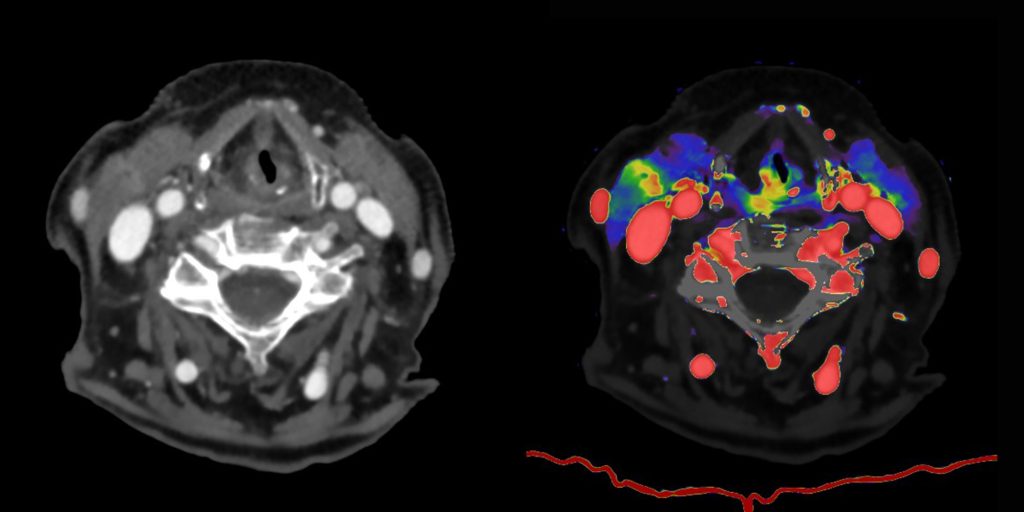

La Spectral CT rappresenta un’evoluzione della tomografia computerizzata (TC) che, grazie all’integrazione di una particolare tecnologia dotata di detettore spettrale Dual Layer, consente di ottenere immagini a colori ad alta definizione e ricche di informazioni, capaci di distinguere con precisione materiali e tessuti e di vedere le strutture anatomiche con un livello di dettaglio e di contenuto superiore.

A differenza delle altre tecnologie TC, la tomografia computerizzata spettrale utilizza fasci ad alta e bassa energia separati a livello del detettore. La parte superficiale del detettore filtra la radiazione a bassa energia, mentre quella sottostante filtra la radiazione ad alta energia. Al contrario, le altre tecnologie oggi disponibili necessitano di due acquisizioni che vengono poi sovrapposte dal dispositivo.